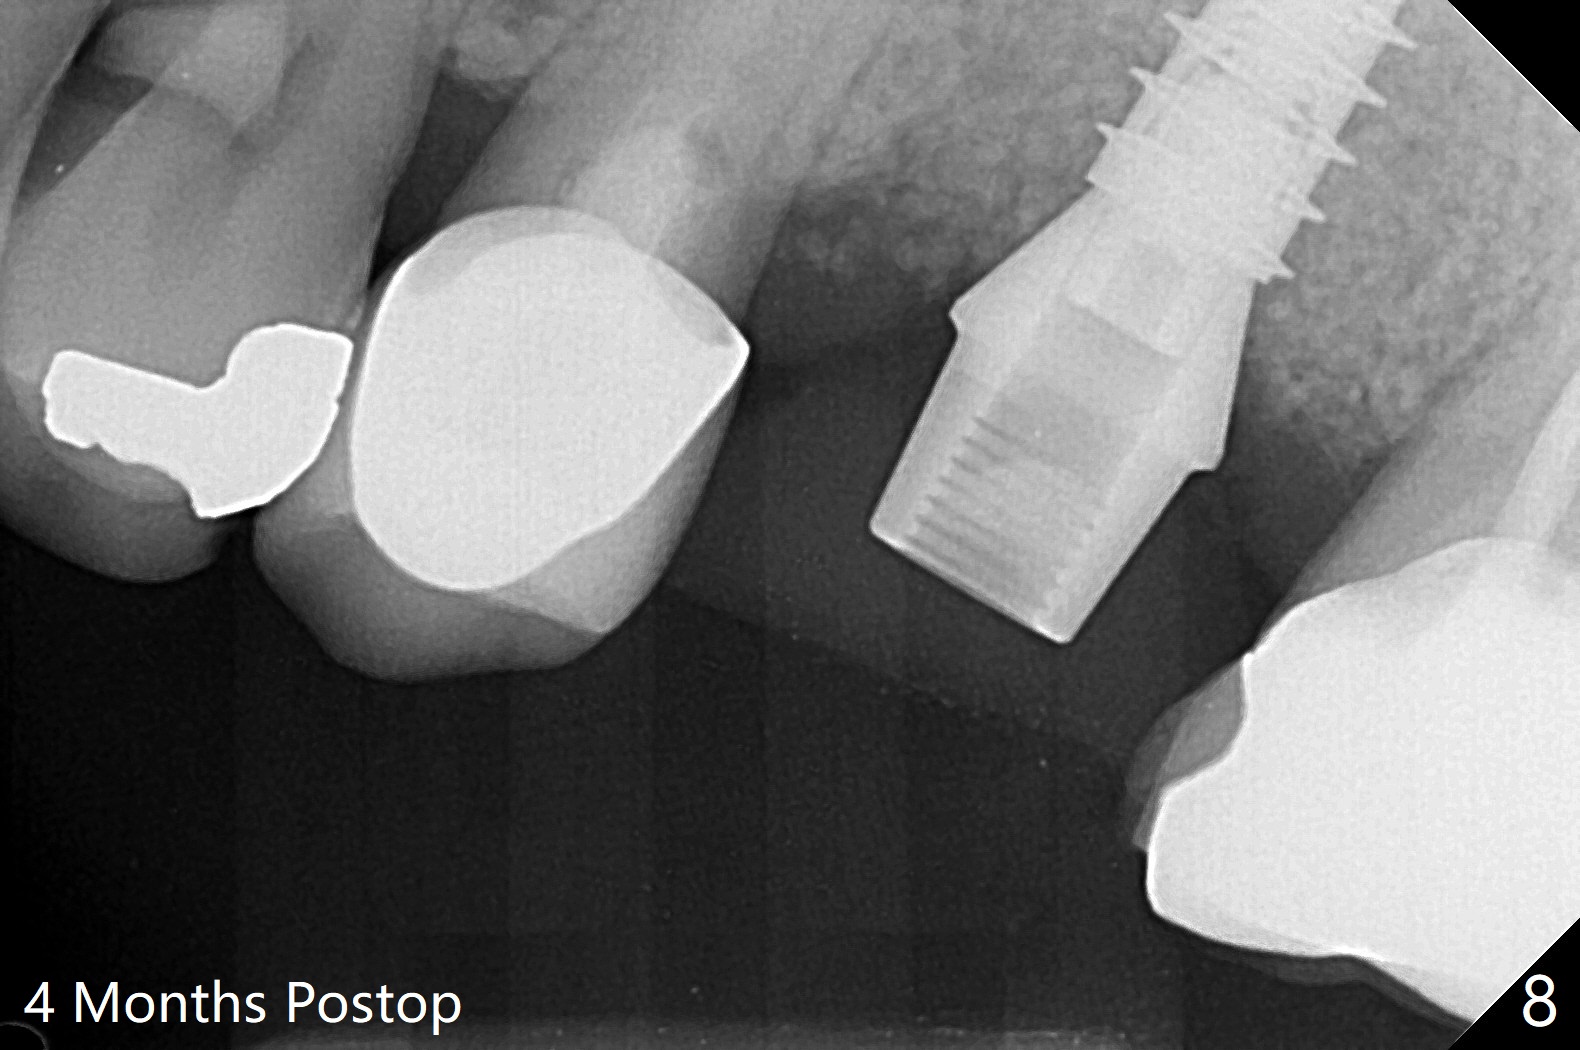

左上6腭侧退缩牙龈(图一:箭头)深部没有骨壁(图二:*),4.5x11毫米植体周围缺损(图三:*)由粘性骨粉(皮质骨,图四:*)填入,即刻临时牙冠(图五:P)覆盖腭侧缺损(空箭头)和PRF膜。临时牙冠颊腭侧做的很宽(图六),目的是关闭腭侧缺损,术后四周在不影响骨粉覆盖情况下,牙冠腭侧适当向颊侧缩小(图七:箭头),但是不应该缩短龈下边缘。术后四个月骨粉形态接近原位骨(图八),但是腭侧软硬组织仍有缺损,炎症。